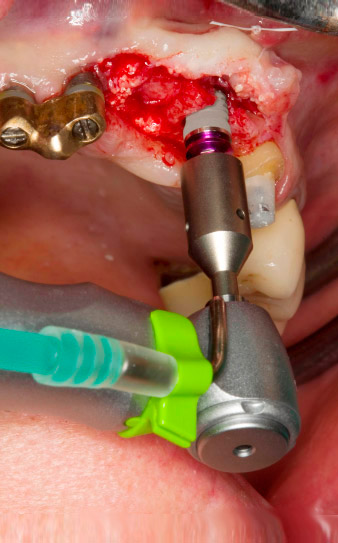

Pose motorisée de l'implant avec le contre-angle

Fig. 4 : Pose motorisée de l'implant avec le contre-angle

WS-75 L suivant un ratio de 20:1 (programme P5).